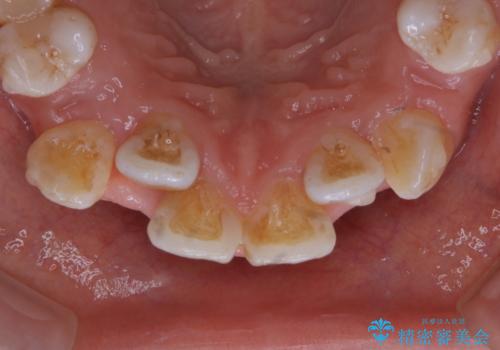

- インビザライン中に、コーヒーによる着色が気になるとのことでした。PMTC60分コースを行いました。

PMTC(保険外治療)は、毎日の歯磨きで落としきれない汚れや、コーヒ、紅茶・タバコのヤニなどの着色も除去します。目には見えない歯と歯の間・歯肉の境目・インビザライン中はアタッチメント周囲などに残っているプラーク(歯垢)もしっかり取り除きます。PMTCでは専門的な機械や材料を使用して、徹底的に汚れを除去するため、虫歯・歯周病・口臭予防などにつながります。

またPMTCを行うことで、ご自身本来の歯の色になり自然な明るさになります。